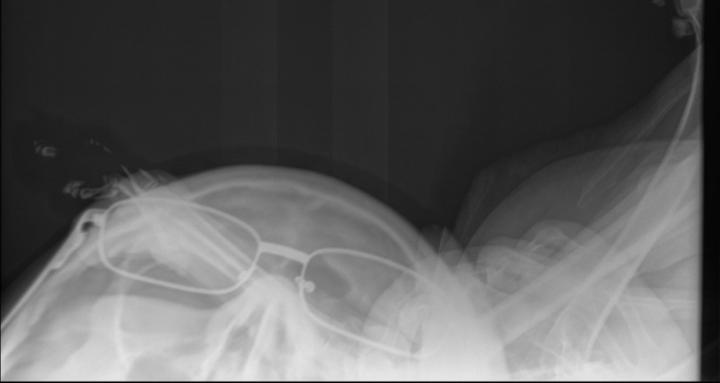

Sage Radiation Safety – Texas is a practical, self-paced certification course for veterinary technicians and veterinarians who operate or assist with X-ray and CT equipment. Designed for real-world clinical use, this course covers radiation biology, cumulative exposure risk, deterministic vs stochastic effects, and the core principles of time, distance, and shielding. You’ll learn how technique choices (kVp, mAs, collimation, positioning) directly impact dose, image quality, and repeat rates. The program also reviews equipment terminology, workflow expectations, dosimetry, PPE use, and essential Texas compliance requirements. With video lessons, knowledge checks, and a final exam, this course provides clear, actionable training to help you reduce exposure, avoid costly mistakes, and protect yourself, your team, and your patients. Participants who pass a 50 question multiple choice final test will receive a certificate of completion and 3 hours of RACE-approved CE.